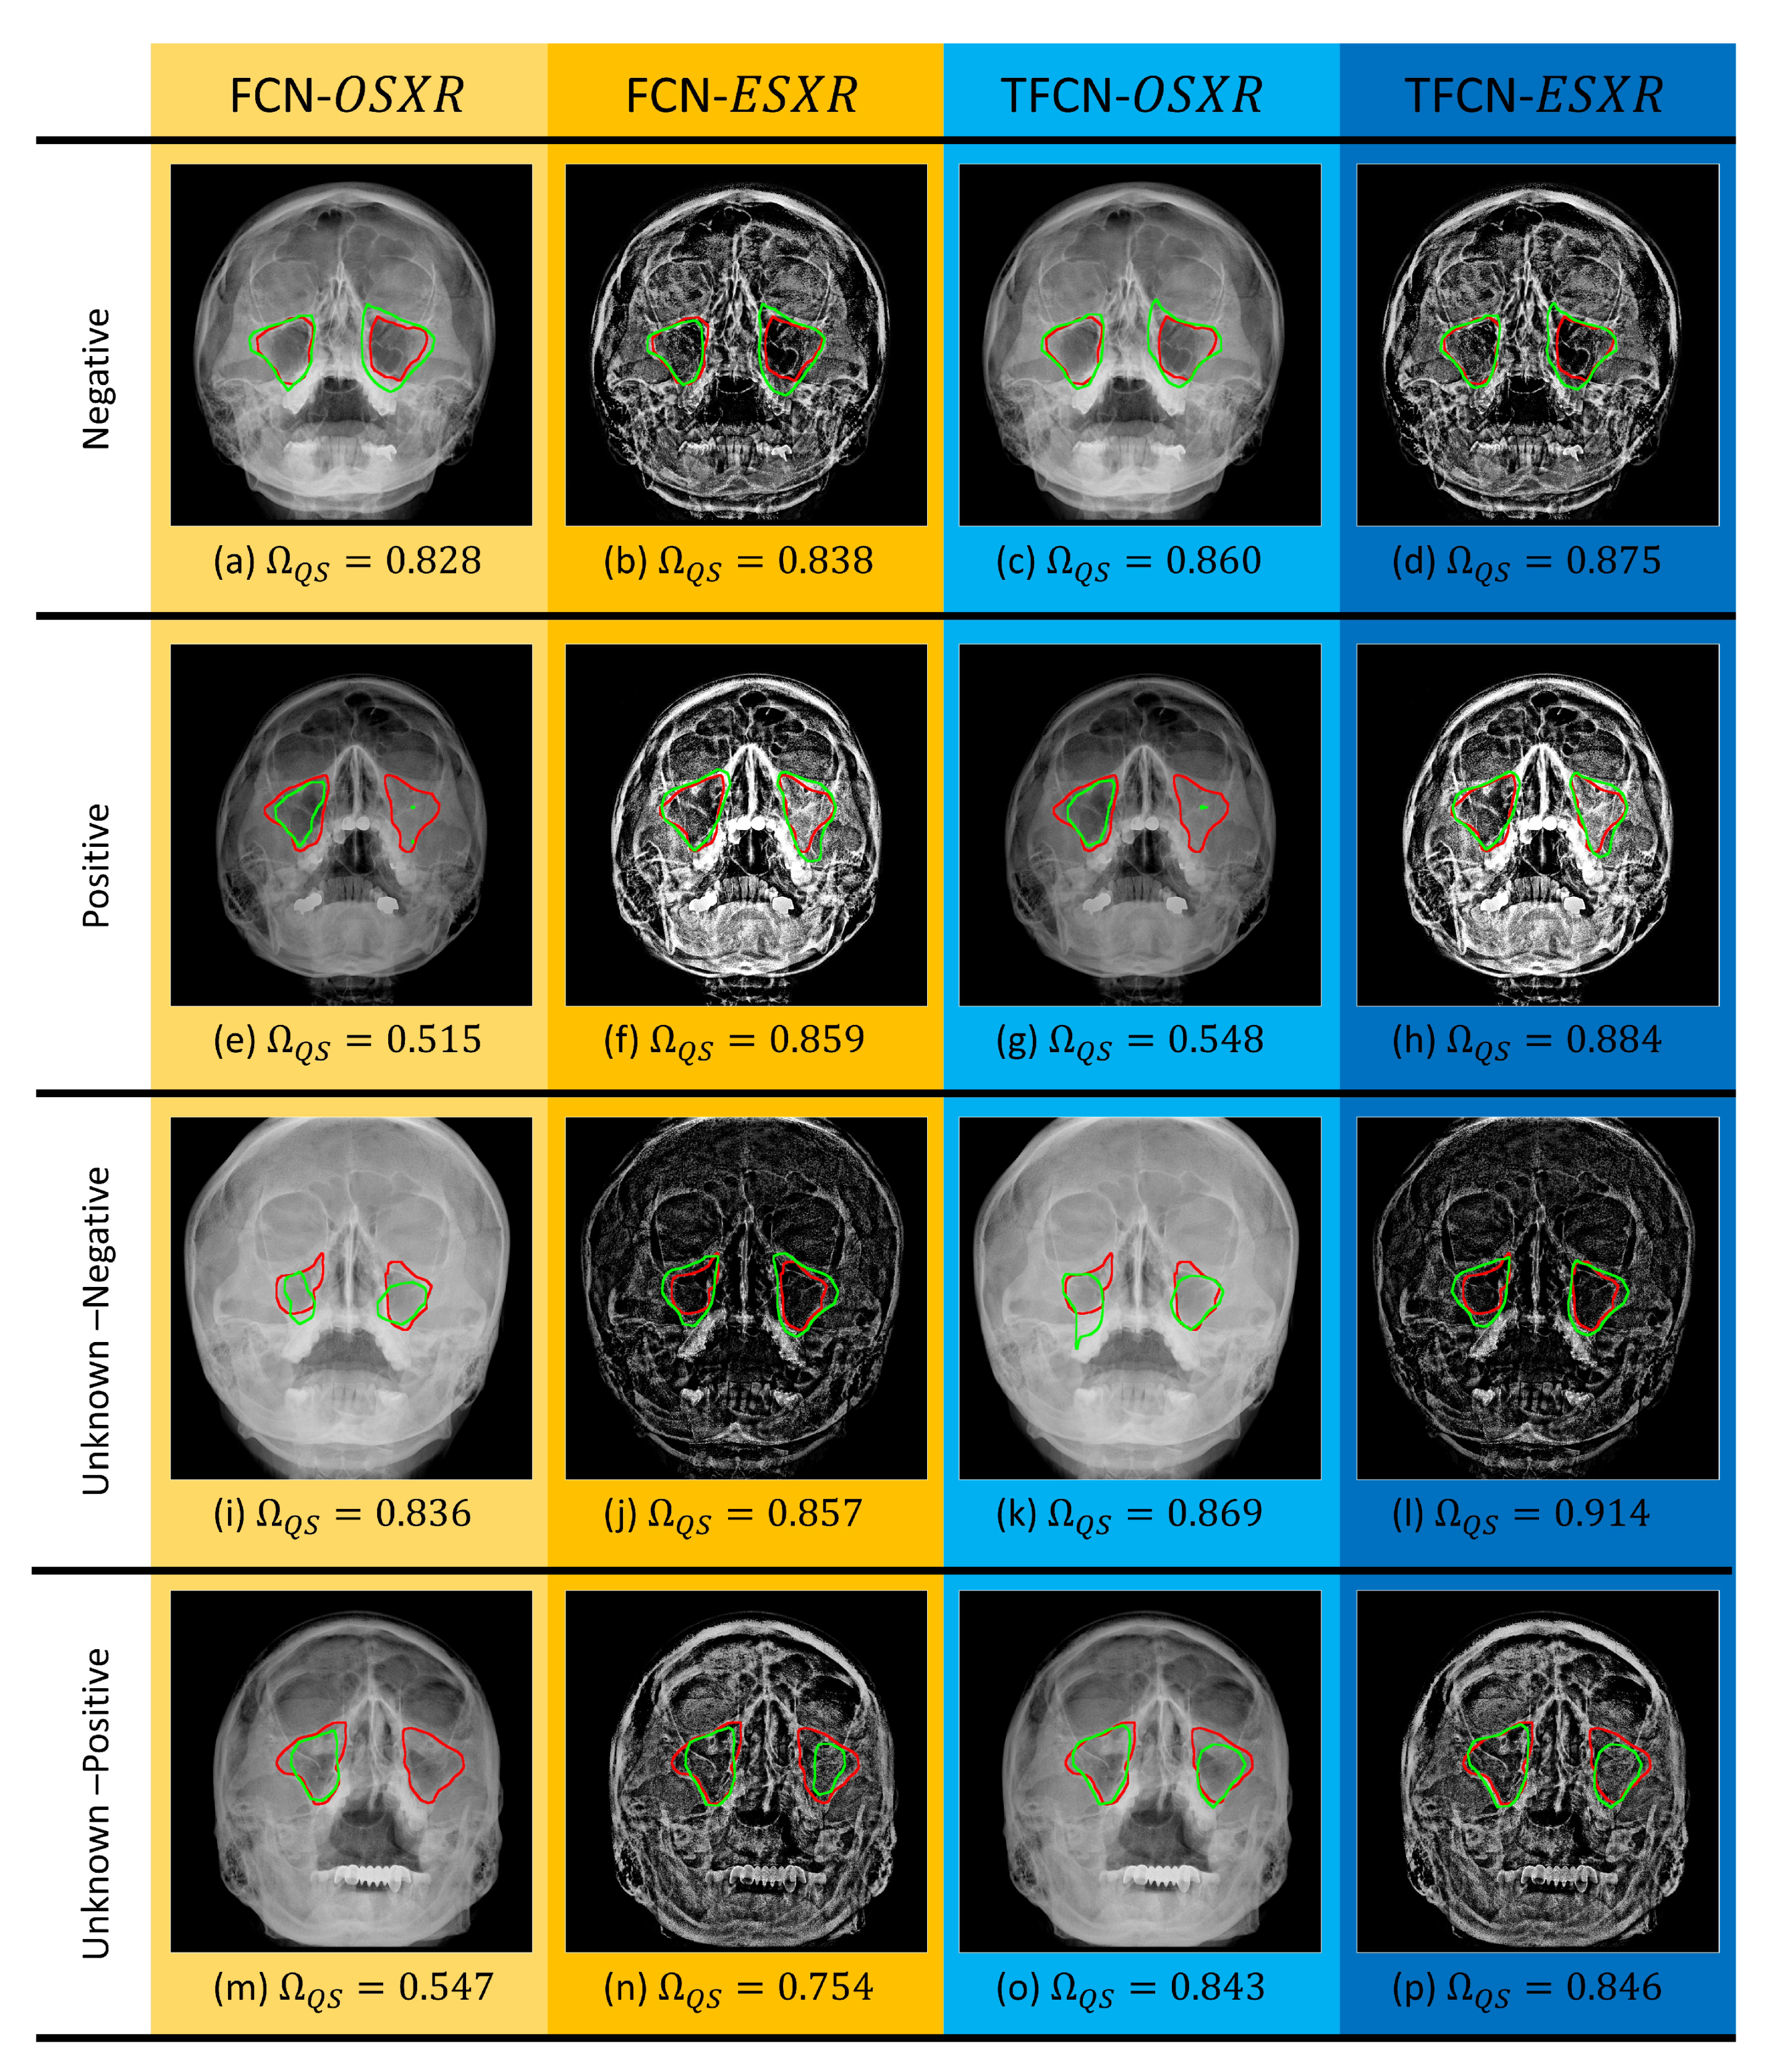

3.4. Image Segmentation Evaluation

Quantitative Evaluation